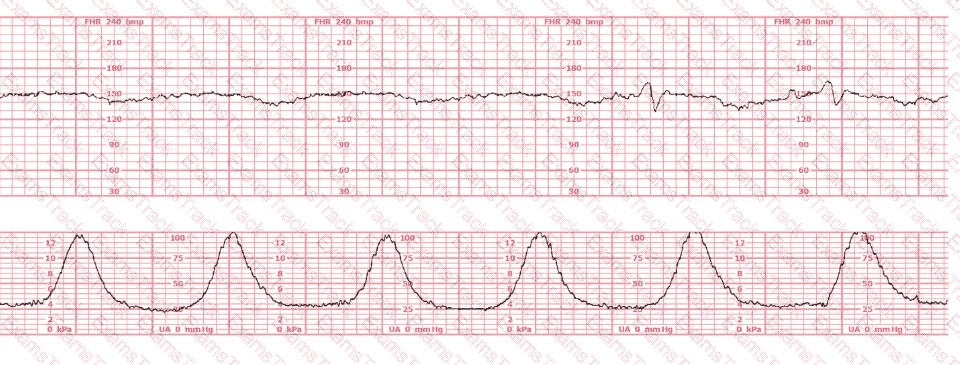

This patient received an epidural 15 minutes prior to the tracing shown. The next course of action is to:

A woman with hypertension at 38-weeks gestation has a biophysical profile. The result is 4/10 with decreased amniotic fluid volume. The next step should be to: